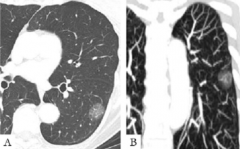

我院“肺部结节(肿瘤)早期诊断门诊”开诊了

随着社会的进步和人们生活水平的提高人们越来越关注自身的健康,...